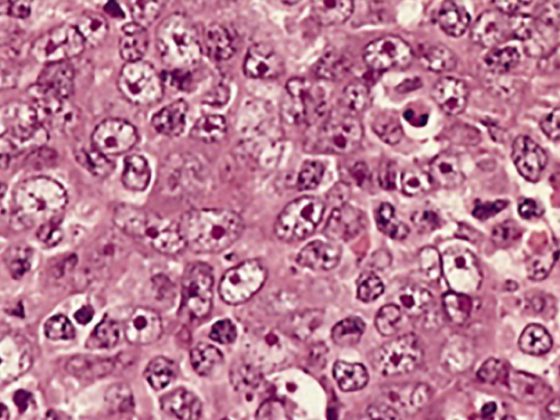

Helle Hautkrebsarten sind die Folge von langjähriger UV-Exposition, mangelndem Sonnenschutz und heller Haut. Basalzell- und Plattenepithelkarzinome gehören zu den häufigsten Hauttumoren und können meistens operativ entfernt werden. Meistens – aber nicht immer.